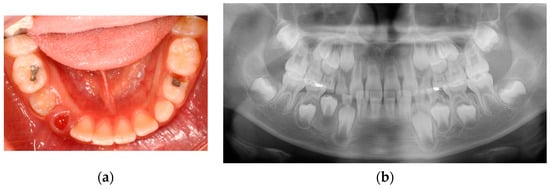

Three days post-treatment, the patient had no complaints, and facial swelling had reduced. Three weeks post-treatment, the facial swelling had nearly subsided, and the RSM was eliminated. Two months post-treatment, the cystic lesion had reduced in size, and the occlusal surface of the mandibular right first premolar was visible intraorally (Figure 9).

Figure 9.

Two months after the marsupialization: (a) intraoral photo; (b) panoramic radiograph.

Four months post-treatment, the bone expansion was remarkably reduced, and dens evaginatus was identified on the premolar. The patient showed no clinical symptoms.